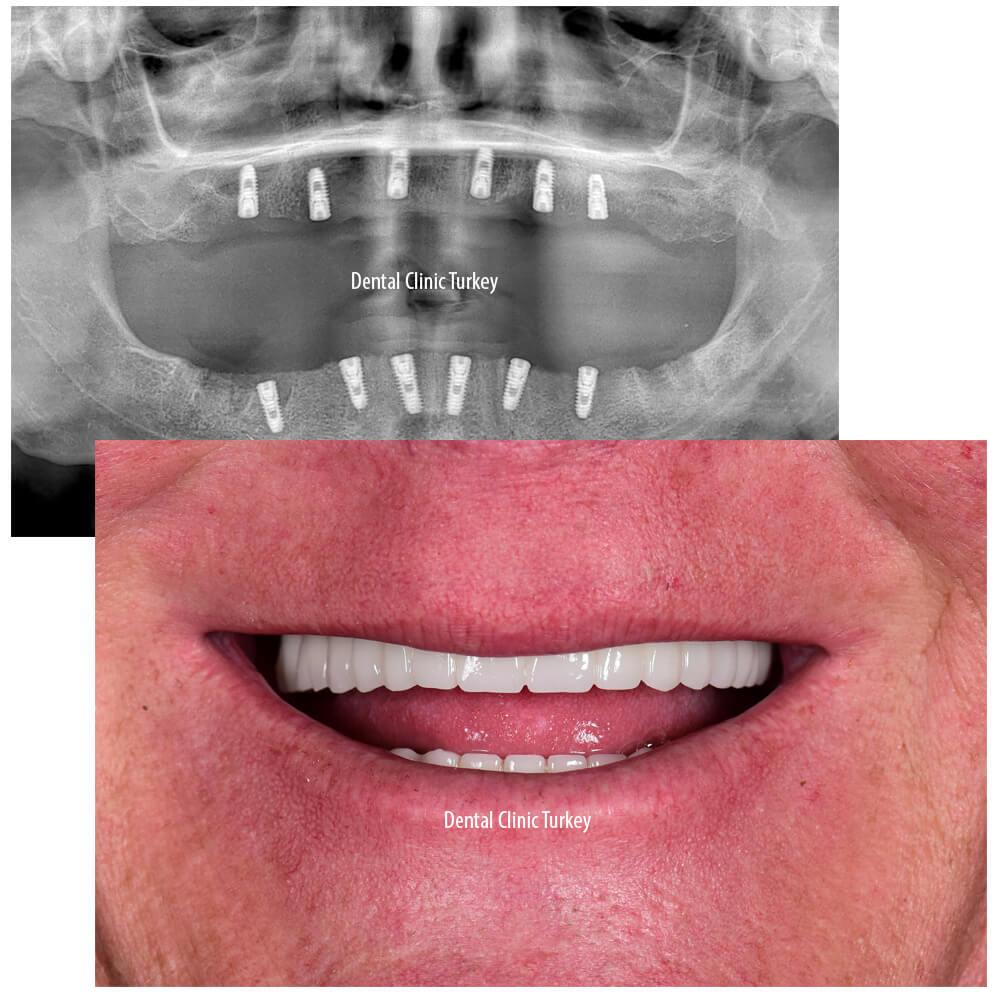

All-on-4 vs. All-on-6 Implants in Antalya: Which is Best for Your Needs, UK Patients?

Considering dental implants in Antalya? Discover the key differences between All-on-4 and All-on-6, tailored for UK patients. Which suits your smile and lifestyle best? Explore your options with confidence!